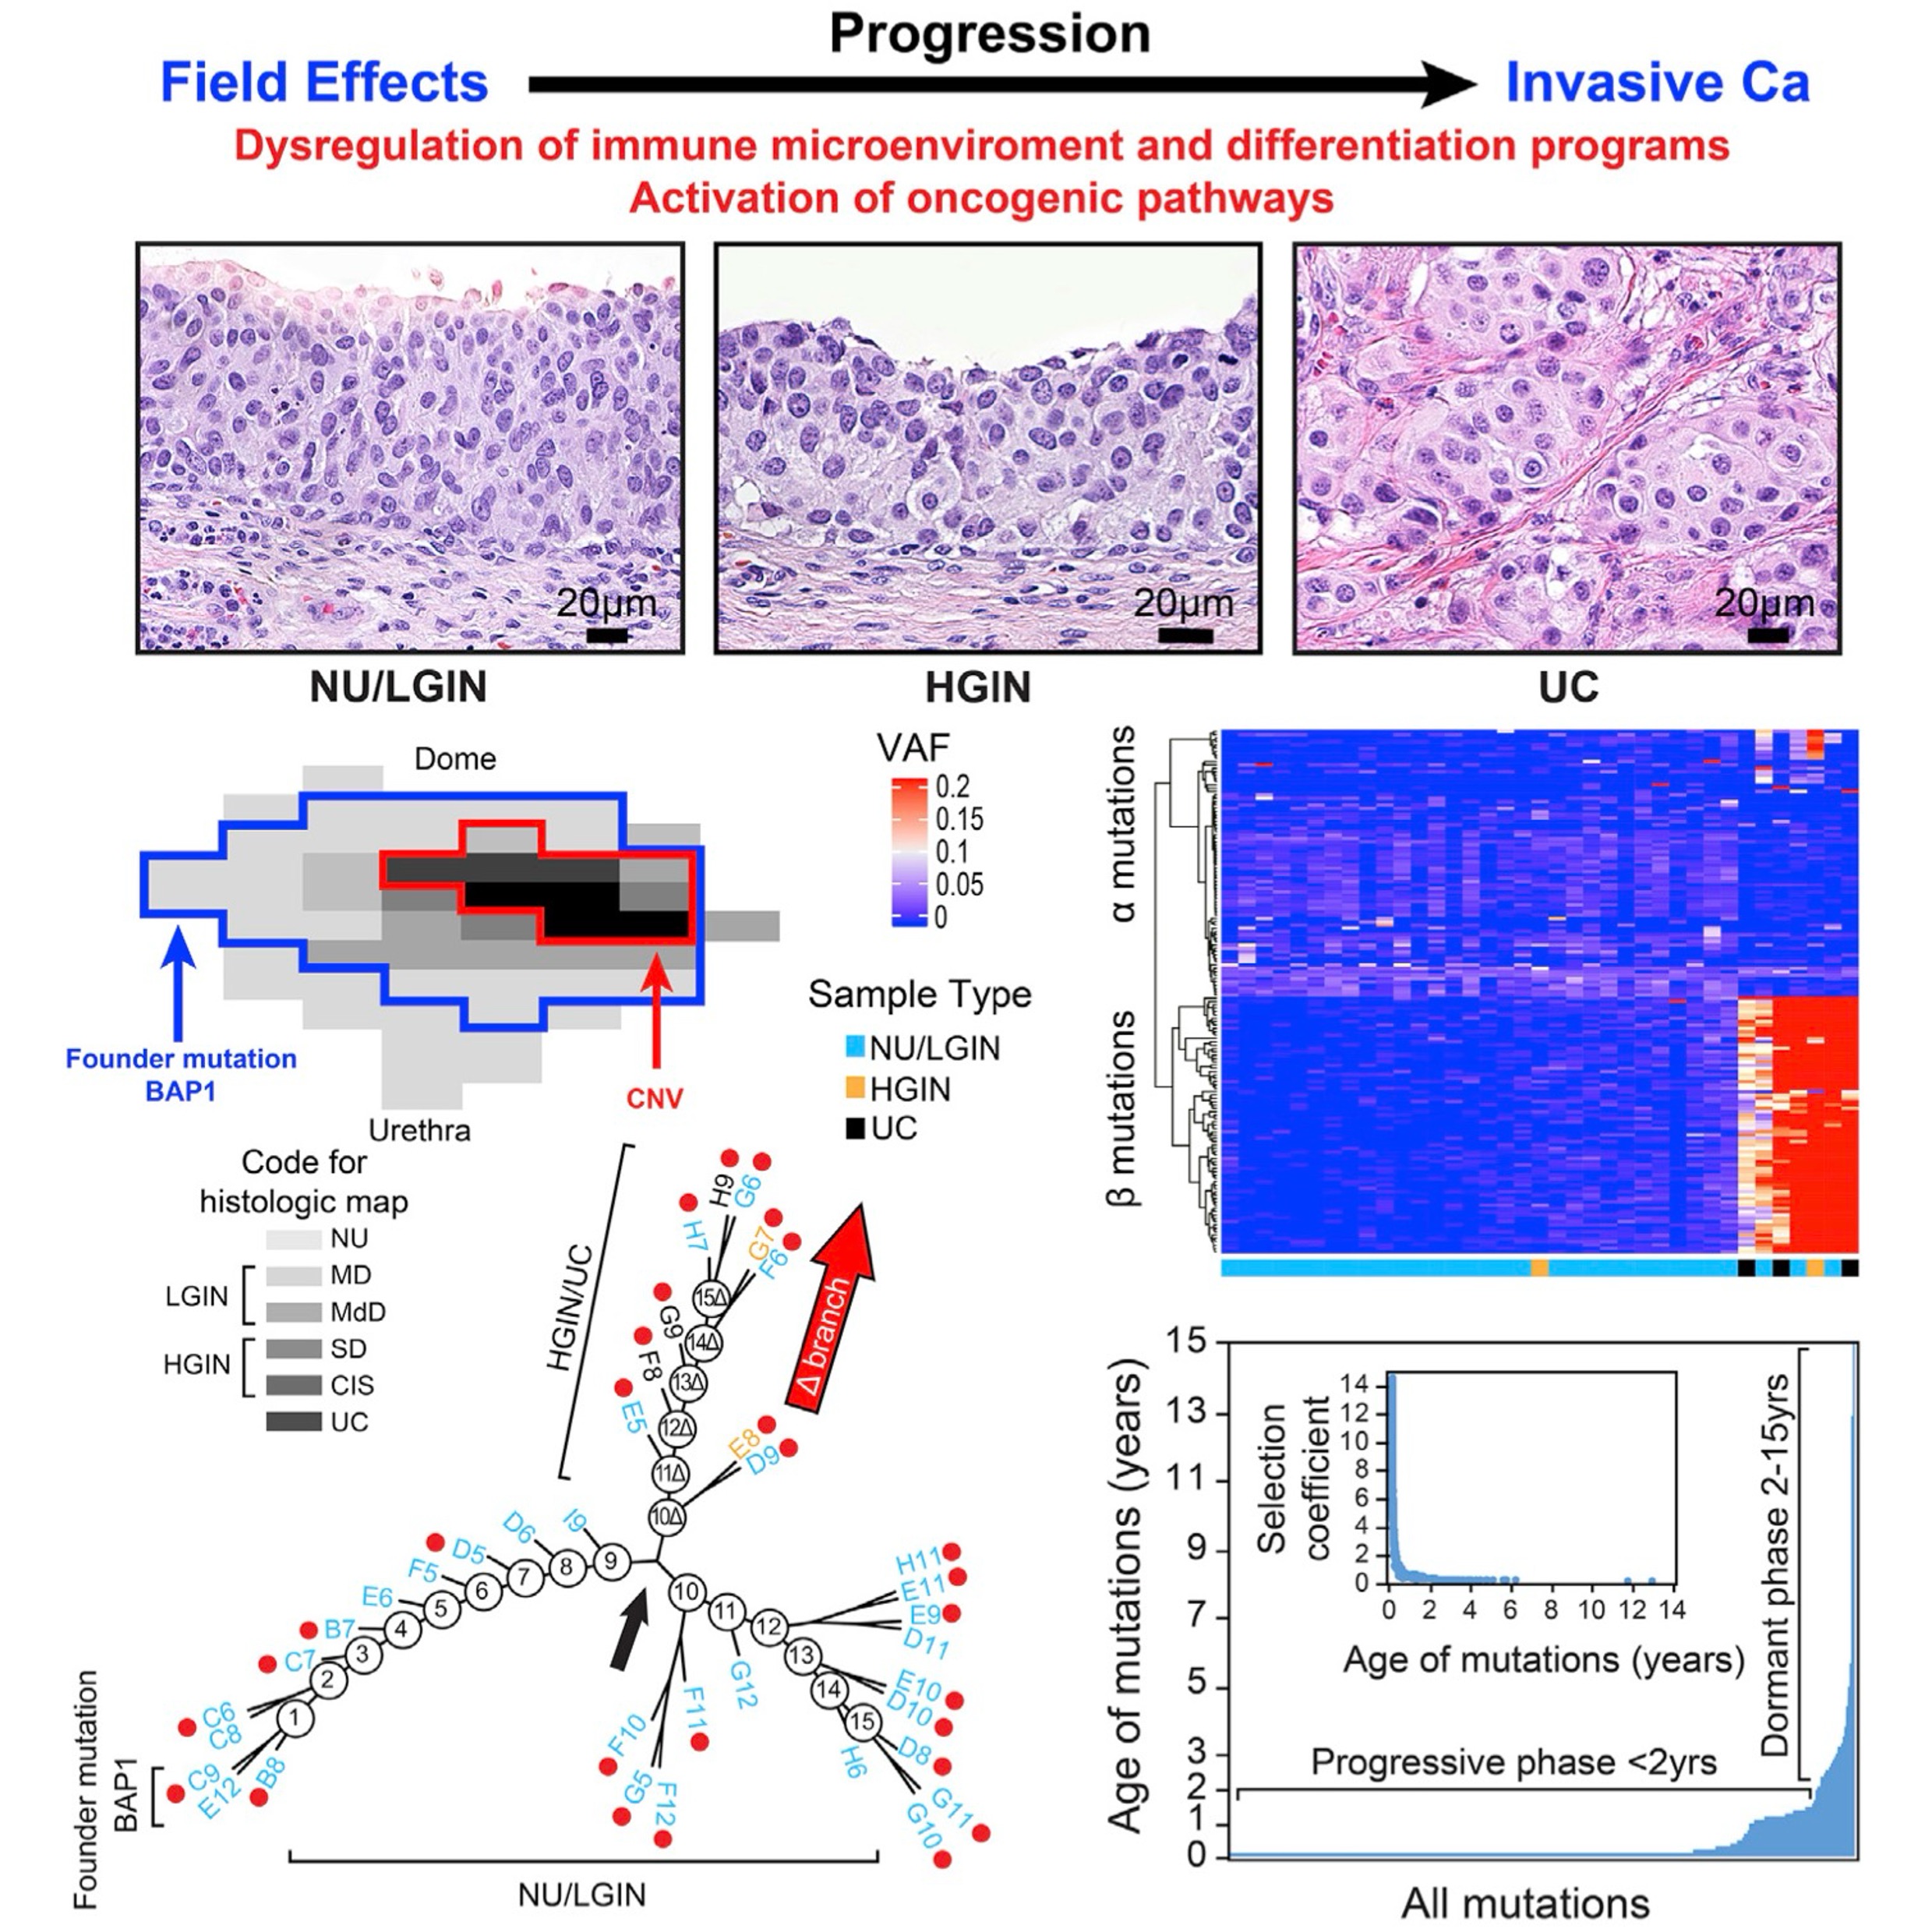

The origin of bladder cancer from mucosal field effectsJolanta Bondaruk, Roman Jaksik, Ziqiao Wang, David Cogdell, Sangkyou Lee, Yujie Chen, Khanh N. Dinh, Tadeusz Majewski, Li Zhang, Shaolong Cao, Feng Tian, Hui Yao, Pawel Kuś, Huiqin Chen, John N. Weinstein, Neema Navai, Colin Dinney, Jianjun Gao, Dan Theodorescu, Christopher Logothetis, Charles C. Guo, Wenyi Wang, David McConkey, Peng Wei, Marek Kimmel, and Bogdan CzerniakiScience, 2022

The origin of bladder cancer from mucosal field effectsJolanta Bondaruk, Roman Jaksik, Ziqiao Wang, David Cogdell, Sangkyou Lee, Yujie Chen, Khanh N. Dinh, Tadeusz Majewski, Li Zhang, Shaolong Cao, Feng Tian, Hui Yao, Pawel Kuś, Huiqin Chen, John N. Weinstein, Neema Navai, Colin Dinney, Jianjun Gao, Dan Theodorescu, Christopher Logothetis, Charles C. Guo, Wenyi Wang, David McConkey, Peng Wei, Marek Kimmel, and Bogdan CzerniakiScience, 2022Whole-organ mapping was used to study molecular changes in the evolution of bladder cancer from field effects. We identified more than 100 dysregulated pathways, involving immunity, differentiation, and transformation, as initiators of carcinogenesis. Dysregulation of interleukins signified the involvement of inflammation in the incipient phases of the process. An aberrant methylation/expression of multiple HOX genes signified dysregulation of the differentiation program. We identified three types of mutations based on their geographic distribution. The most common were mutations restricted to individual mucosal samples that targeted uroprogenitor cells. Two types of mutations were associated with clonal expansion and involved large areas of mucosa. The αmutations occurred at low frequencies while the βmutations increased in frequency with disease progression. Modeling revealed that bladder carcinogenesis spans 10-15 years and can be divided into dormant and progressive phases. The progressive phase lasted 1-2 years and was driven by βmutations.

Dysregulated mitochondrial energy metabolism drives the progression of mucosal field effects to invasive bladder cancerSangkyou Lee, Sung Yun Jung, Pawel Kuś, Jolanta Bondaruk, June Goo Lee, Roman Jaksik, Nagireddy Putluri, Khanh N. Dinh, David Cogdell, Huiqin Chen, Yishan Wang, Jiansong Chen, Neema Navai, Colin Dinney, Cathy Mendelsohn, David McConkey, Richard R. Behringer, Charles C. Guo, Peng Wei, Marek Kimmel, and Bogdan CzerniakThe Journal of Pathology. Highlighted in Nature Reviews Urology , 2025

Dysregulated mitochondrial energy metabolism drives the progression of mucosal field effects to invasive bladder cancerSangkyou Lee, Sung Yun Jung, Pawel Kuś, Jolanta Bondaruk, June Goo Lee, Roman Jaksik, Nagireddy Putluri, Khanh N. Dinh, David Cogdell, Huiqin Chen, Yishan Wang, Jiansong Chen, Neema Navai, Colin Dinney, Cathy Mendelsohn, David McConkey, Richard R. Behringer, Charles C. Guo, Peng Wei, Marek Kimmel, and Bogdan CzerniakThe Journal of Pathology. Highlighted in Nature Reviews Urology , 2025Multiplatform mutational and gene expression profiling complemented with proteomic and metabolomic spatial mapping were used on the whole-organ scale to identify the molecular profile of bladder cancer evolution from field effects. Analysis of the mutational landscape identified three types of mutations, referred to as alpha, beta, and gamma. Time modeling of the mutations revealed that carcinogenesis may span 30 years and can be divided into dormant and progressive phases. The alpha mutations developed in the dormant phase. The progressive phase lasted 5 years and was signified by expanding beta mutations, but it was driven to invasive cancer by gamma mutations. The mutational landscape emerged on a background of disorganized urothelial differentiation, activated epithelial-mesenchymal transition, and enhanced immune infiltration with T-cell exhaustion. Complex dysregulation of mitochondrial energy metabolism with downregulation of oxidative phosphorylation emerged as the leading mechanism driving the progression of mucosal field effects to invasive cancer.